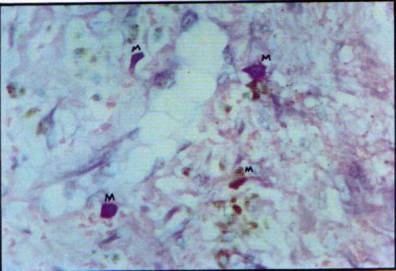

Foto

12: Abundantes mastocitos concentrados en el estroma modificado peritumoral (M)

Por otra parte la presencia de abundantes mastocitos evidenciados con

la técnica de Giemsa nos induce a pensar en IL 3, factor producido por células

"T', activadas que tiene importante acción en la atracción y diferenciación

de BMMC (Bone marrow mast cell) y MMC (Mucosal mast cell) hacia CTMC (Conective

tissue mast cell) estas últimas íntimamente asociadas a los fibroblastos a los

que induce a fabricar Globopentanosileeramida, la

que incorporan a su membrana celular.